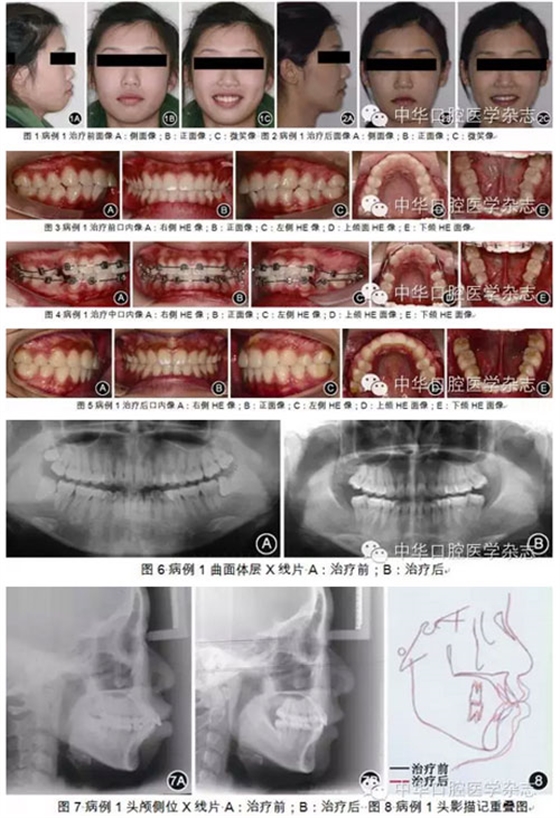

理解骨骼類(lèi)型:正畸診斷和治療必須與生長(zhǎng)發(fā)育協(xié)調(diào);對(duì)于異常的生長(zhǎng)型,須采取必要的措施進(jìn)行調(diào)整或補(bǔ)償。因此,個(gè)性化診斷時(shí)需從以下5個(gè)方面進(jìn)行綜合分析,即面部美觀(guān)、骨骼類(lèi)型、牙量與骨量不調(diào)、矢狀向關(guān)系不調(diào)和生長(zhǎng)發(fā)育。首先需對(duì)患者正側(cè)貌進(jìn)行整體評(píng)估,對(duì)面形理想的患者,治療時(shí)應(yīng)維持。側(cè)貌受3方面因素影響:①牙齒位置,上切牙位置直接影響唇的位置:上下唇均由上切牙支撐,且上下切牙位置密切相關(guān),牙齒位置直接影響唇的突度,進(jìn)而影響面形。②骨骼結(jié)構(gòu),正畸醫(yī)師應(yīng)意識(shí)到骨骼結(jié)構(gòu)的異常也是面部失衡的重要因素,一定程度的骨骼結(jié)構(gòu)異??赏ㄟ^(guò)改變牙齒位置代償。對(duì)于下頜平面角(FMA)為高角的患者,可通過(guò)更多地直立下切牙代償骨骼異常,改善面形。而對(duì)于下頜平面角為低角的患者,下切牙則可維持在原來(lái)相對(duì)唇傾的位置。因此,下頜平面角、后面高(PFH)、前面高(AFH)及PFH/AFH等骨骼結(jié)構(gòu)垂直向測(cè)量項(xiàng)目在個(gè)性化診斷系統(tǒng)中十分重要。③軟組織厚度,在和諧的面形中,唇厚度與頦厚度常一致;若頦厚度不足,則需進(jìn)一步直立下切牙代償。充分分析牙齒位置、骨骼結(jié)構(gòu)以及軟組織情況,可幫助正畸醫(yī)師獲得更多的關(guān)于面部美觀(guān)的信息,有助于判斷是否可通過(guò)牙齒代償改善面形。分析側(cè)貌形態(tài)時(shí)通過(guò)Z線(xiàn)(側(cè)貌線(xiàn))可客觀(guān)判斷面部突度。Z線(xiàn)為連接頦部和唇部最突點(diǎn)的連線(xiàn),其與眶耳平面所形成的后下角為Z角。正常的Z角為70°~80°,理想值為75°~78°。作為FMIA角的外在表現(xiàn),Z角在評(píng)價(jià)軟組織側(cè)貌時(shí)敏感性高,是下頜平面角、FMIA角和軟組織厚度3個(gè)指標(biāo)的綜合體現(xiàn)。骨骼結(jié)構(gòu)分析應(yīng)從以下幾方面進(jìn)行:①下頜平面角,下頜平面角是顱頜面骨骼分析中重要的測(cè)量項(xiàng)目,其可同時(shí)反映面下1/3的垂直向和矢狀向生長(zhǎng),正常范圍為22°~28°。PFH、AFH及PFH/AFH則是面下1/3垂直高度更直接的測(cè)量指標(biāo)。高角患者需要牙齒更大程度的舌向直立代償,治療難度也較大。②SNA角、SNB角、ANB角反映了上下頜骨相對(duì)于顱底及其矢狀向位置,而AO-BO距(Wits值)在代表上下頜骨矢狀向相對(duì)位置方面,比ANB角更敏感。除面部和骨骼因素外,牙量與骨量不調(diào)也需認(rèn)真考量??谇蝗S空間內(nèi)牙列的大小是有限的,即牙列的前部、后部、側(cè)方和垂直界限。在牙列三維空間的框架內(nèi)分別測(cè)量矯治前、中、后段所需的間隙,包括擁擠量及直立切牙改善面形所需的間隙。上下頜牙列矢狀向關(guān)系不調(diào)主要涉及磨牙關(guān)系不調(diào),矯正Ⅱ類(lèi)或Ⅲ類(lèi)磨牙關(guān)系均需間隙。測(cè)量方法為上頜第一前磨牙頰尖至下頜第一、第二前磨牙鄰接隙間距離。生長(zhǎng)發(fā)育也是診斷中需考慮的因素。青少年下頜升支因生長(zhǎng)向后改建,從而增加間隙。男性16歲和女性14歲前,每年可增加3 mm的間隙,之后則基本無(wú)增加可能。以上顱面形態(tài)分析和全牙列間隙分析共同構(gòu)成了個(gè)性化診斷系統(tǒng)。臨床上,根據(jù)Z角判斷側(cè)貌,決定是否需通過(guò)內(nèi)收直立下切牙改變FMIA角來(lái)改變患者側(cè)貌,再根據(jù)顱面垂直向(高角或低角)和軟組織形態(tài)決定如何改變患者側(cè)貌:當(dāng)下頜平面角正常時(shí),F(xiàn)MIA角應(yīng)為68°;當(dāng)下頜平面角>28°時(shí),下前牙則應(yīng)更直立代償,F(xiàn)MIA角為65°。頦部軟組織厚度不夠時(shí)下切牙也應(yīng)適度代償直立。FMIA角每增大1°,則需要0.8 mm的間隙。而顱面骨骼矢狀向是否正常(SNA角、SNB角、ANB角、Wits值)決定是否需對(duì)治療目標(biāo)進(jìn)行一定程度的妥協(xié),減少下切牙的移動(dòng)量。根據(jù)以上項(xiàng)目結(jié)合全牙列間隙分析、磨牙關(guān)系、患者生長(zhǎng)發(fā)育潛力,就能明確治療錯(cuò)HE畸形所需的間隙,從而為臨床醫(yī)師確定減數(shù)方案提供定量參考。經(jīng)典方絲弓矯治技術(shù)個(gè)性化診斷系統(tǒng)還包括治療難度的評(píng)估。Gramling通過(guò)對(duì)安氏Ⅱ類(lèi)錯(cuò)HE矯治與否進(jìn)行分組對(duì)比,分析顱頜面?zhèn)让残螒B(tài)、牙列及牙列關(guān)系對(duì)療效的影響,得出各測(cè)量項(xiàng)目偏離正常值時(shí)對(duì)畸形治療難度的貢獻(xiàn)權(quán)重及難度系數(shù)。測(cè)量分析中超出正常范圍的數(shù)值乘上相應(yīng)難度系數(shù)構(gòu)成難度指數(shù)。顱面形態(tài)的難度指數(shù)以及全牙列間隙的難度指數(shù)共同組成總的難度指數(shù),其為治療預(yù)后的評(píng)估、治療過(guò)程的管理有重要指導(dǎo)意義。圖1~8所示患者為牙型Ⅰ類(lèi)、骨型Ⅱ類(lèi)、嚴(yán)重雙頜前突、露齦笑的20歲女性,顱面分析難度指數(shù)為64,顱面及牙列總難度指數(shù)合計(jì)為97.75,說(shuō)明患者矯治難度中等。牙列間隙分析顯示排齊內(nèi)收前牙需19 mm間隙,而全牙列間隙不足共37.5 mm,根據(jù)經(jīng)典方絲弓個(gè)性化診斷系統(tǒng),提示患者需減數(shù)4顆第一前磨牙和4顆第三磨牙。采用定向力矯治技術(shù)治療后患者面形協(xié)調(diào)。下頜平面角和PFH/AFH得到較好的保持。下切牙從108.5°直立到90°,上切牙得到內(nèi)收并壓低。Z角從50.5°增加至72.5°。因此,經(jīng)典方絲弓定向力矯治技術(shù)中的個(gè)性化診斷系統(tǒng)是內(nèi)容全面、使用方便的診斷分析系統(tǒng),為正畸醫(yī)師提供了清晰的治療路線(xiàn)圖。任何治療技術(shù)都是為了實(shí)現(xiàn)其治療理念所設(shè)計(jì)的。以Tweed醫(yī)師的治療目標(biāo)和治療理念為基礎(chǔ),Merrifield醫(yī)師將原來(lái)的12組弓絲簡(jiǎn)化為4~5組弓絲,凝練成簡(jiǎn)單、高效而原理更完善的定向力矯治技術(shù),其具有以下特點(diǎn)。1.按順序分次粘接矯治器和按順序分次移動(dòng)牙齒對(duì)減數(shù)第一前磨牙的病例,第一恒磨牙暫時(shí)不粘接矯治器,錯(cuò)位嚴(yán)重的前牙也可暫時(shí)不結(jié)扎或僅做被動(dòng)結(jié)扎。由此第二前磨牙至第二恒磨牙的托槽間距較長(zhǎng),可使弓絲更有效地作用于第二恒磨牙;患者感覺(jué)舒適,也可節(jié)省醫(yī)師的椅旁時(shí)間。隨著第二恒磨牙位置逐漸遠(yuǎn)中直立,分別在1、2個(gè)月后粘接上頜第一恒磨牙、下頜第一恒磨牙托槽。使牙齒在有效的控制下快速而精確地分次定向移動(dòng)。Tweed醫(yī)師嘗試用Ⅲ類(lèi)牽引對(duì)所有下頜后牙進(jìn)行一次性支抗預(yù)備,雖然部分病例取得成功,但常導(dǎo)致下頜前牙唇向傾斜壓低。Merrifield醫(yī)師采用高位J鉤牽引和10顆牙作為支抗,每次移動(dòng)2顆牙,使支抗預(yù)備更可控、有序而精確,稱(chēng)為Merrifield的“10-2”支抗預(yù)備技術(shù)。在治療初期牙列預(yù)備階段,下頜第二恒磨牙已被直立后傾至合適位置,下牙列分別通過(guò)尖牙遠(yuǎn)中移動(dòng)和垂直曲內(nèi)收切牙關(guān)閉拔牙間隙,再依次進(jìn)行下頜第一恒磨牙和第二前磨牙的支抗預(yù)備。3.使用定向力系統(tǒng)控制牙移動(dòng)是經(jīng)典方絲弓矯治技術(shù)的精髓和重要標(biāo)志所謂定向力矯治系統(tǒng),即所有矯治力均應(yīng)引導(dǎo)患者牙列和頜骨產(chǎn)生治療所需反應(yīng),而避免矯治力的不良反應(yīng)。弓絲和牽引力的作用應(yīng)相互協(xié)同,對(duì)于未成年患者,矯治力的治療作用應(yīng)與生長(zhǎng)發(fā)育協(xié)調(diào);對(duì)于成年患者,治療作用則不應(yīng)干擾牙列與其周邊環(huán)境的正常關(guān)系,使下頜平面、HE平面、腭平面與眶耳平面的關(guān)系保持不變或?qū)⒆兓刂朴谶m度范圍內(nèi)。治療時(shí)發(fā)現(xiàn)不良變化應(yīng)及時(shí)調(diào)整矯治力。當(dāng)然,對(duì)于Ⅲ類(lèi)錯(cuò)HE或下頜平面角為低角等需要垂直向擴(kuò)張、下頜平面后下旋轉(zhuǎn)的患者,則可采用不同的矯治力系統(tǒng)。正畸矯治力若不加以控制則可產(chǎn)生不良作用。由于牙齒本身有HE向萌出和近中移動(dòng)趨勢(shì),未加控制的整平可引起磨牙升高;天然牙列下頜磨牙常前傾而有Spee曲度,矯治時(shí)若不預(yù)先直立而直接施加頜內(nèi)矯治力,作為支抗的磨牙則易前傾升高,Ⅱ類(lèi)牽引的垂直向分力則可加劇下頜磨牙的升高。以上作用均可使下頜向后向下旋轉(zhuǎn),產(chǎn)生頦部后縮、下前牙唇傾、面下1/3變